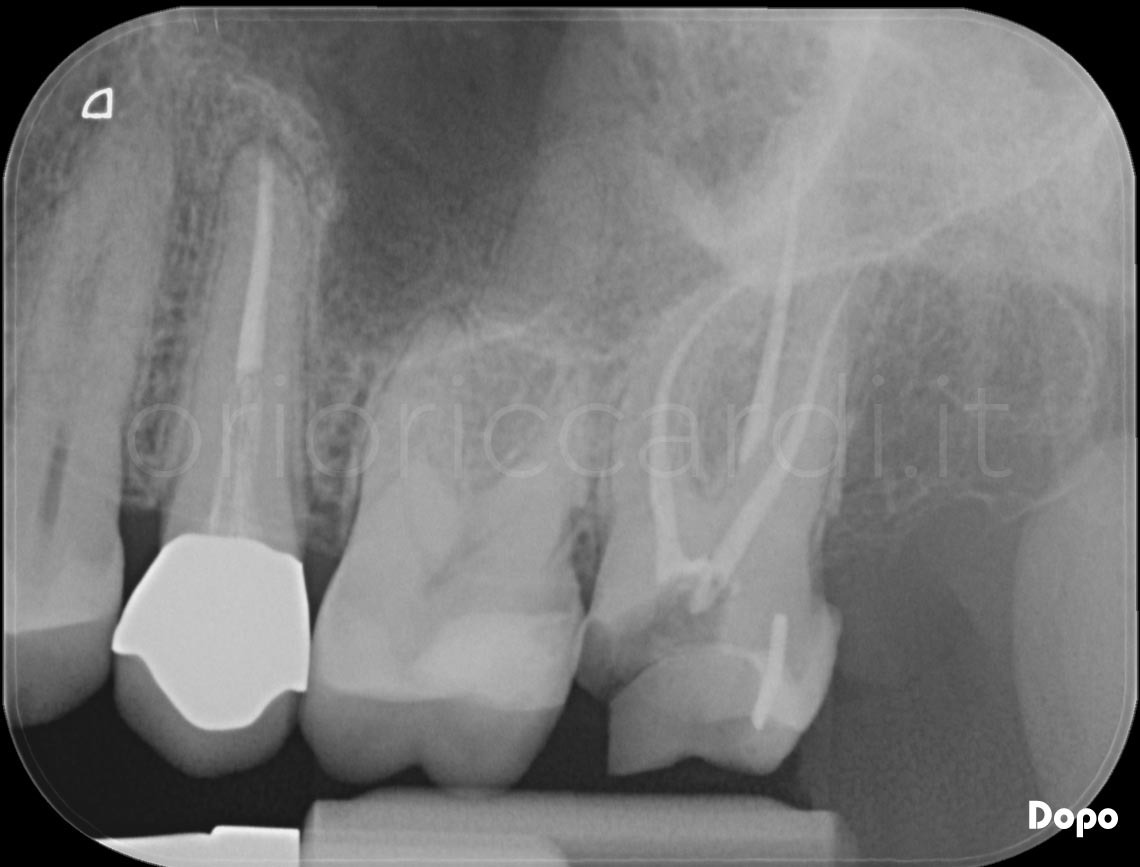

Carie penetranti o traumi possono danneggiarla irreversibilmente e quindi è richiesta la sua rimozione ossia la devitalizzazione o terapia canalare. Essa consiste nella detersione , disinfezione , sagomatura dei canali radicolari e della loro completa sigillatura. Il tutto viene eseguito sempre con l’utilizzo della diga di gomma. La realizzazione di una terapia endodontica richiede l’esecuzione di alcune radiografie endorali e nei casi più complessi di immagini tridimensionali CBCT ENDO.